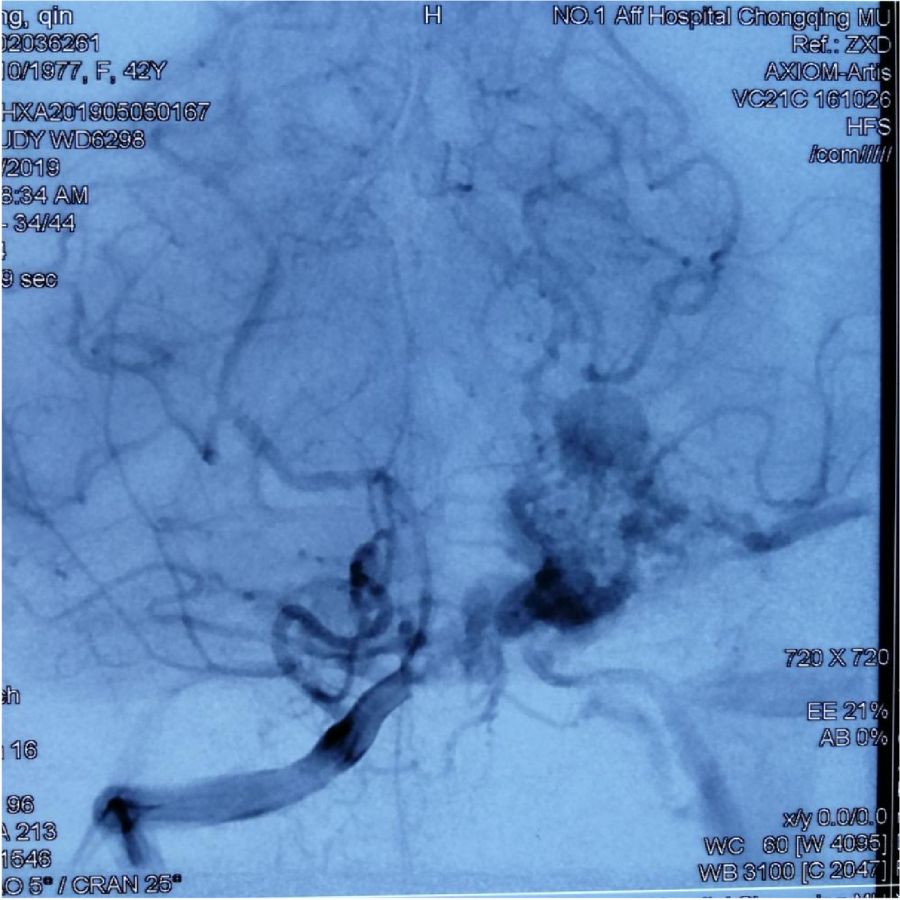

第⼀次DSA显⽰PICA供⾎

引流⾄⼄状窦

小脑后下动脉、小脑前下动脉参与供⾎

本次⼊院⾏DSA检查:PICA供⾎区有畸形⾎管团,引流到横窦